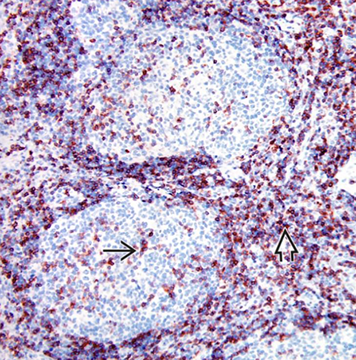

CD3 in reactive follicles. Immunohistochemical stain for the pan T-cell marker CD3 highlights scattered small lymphocytes within germinal centers (solid black line). Many more CD3(+) lymphocytes are noted in the interfollicular region .(open black line) [2]